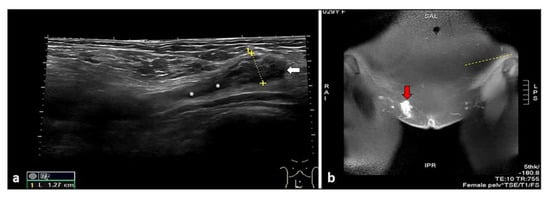

- Cocco, G.; Ricci, V.; Boccatonda, A.; Schiavone, C. Focused ultrasound for the diagnosis of non-palpable endometriotic lesions of the abdominal wall: A not-uncommon surgical complication. J. Ultrasound 2020, 23, 183–187. [Google Scholar] [CrossRef] [PubMed]

- Bozkurt, M.; Çil, A.S.; Bozkurt, D.K. Intramuscular abdominal wall endometriosis treated by ultrasound-guided ethanol injection. Clin. Med. Res. 2014, 12, 160–165. [Google Scholar] [CrossRef]